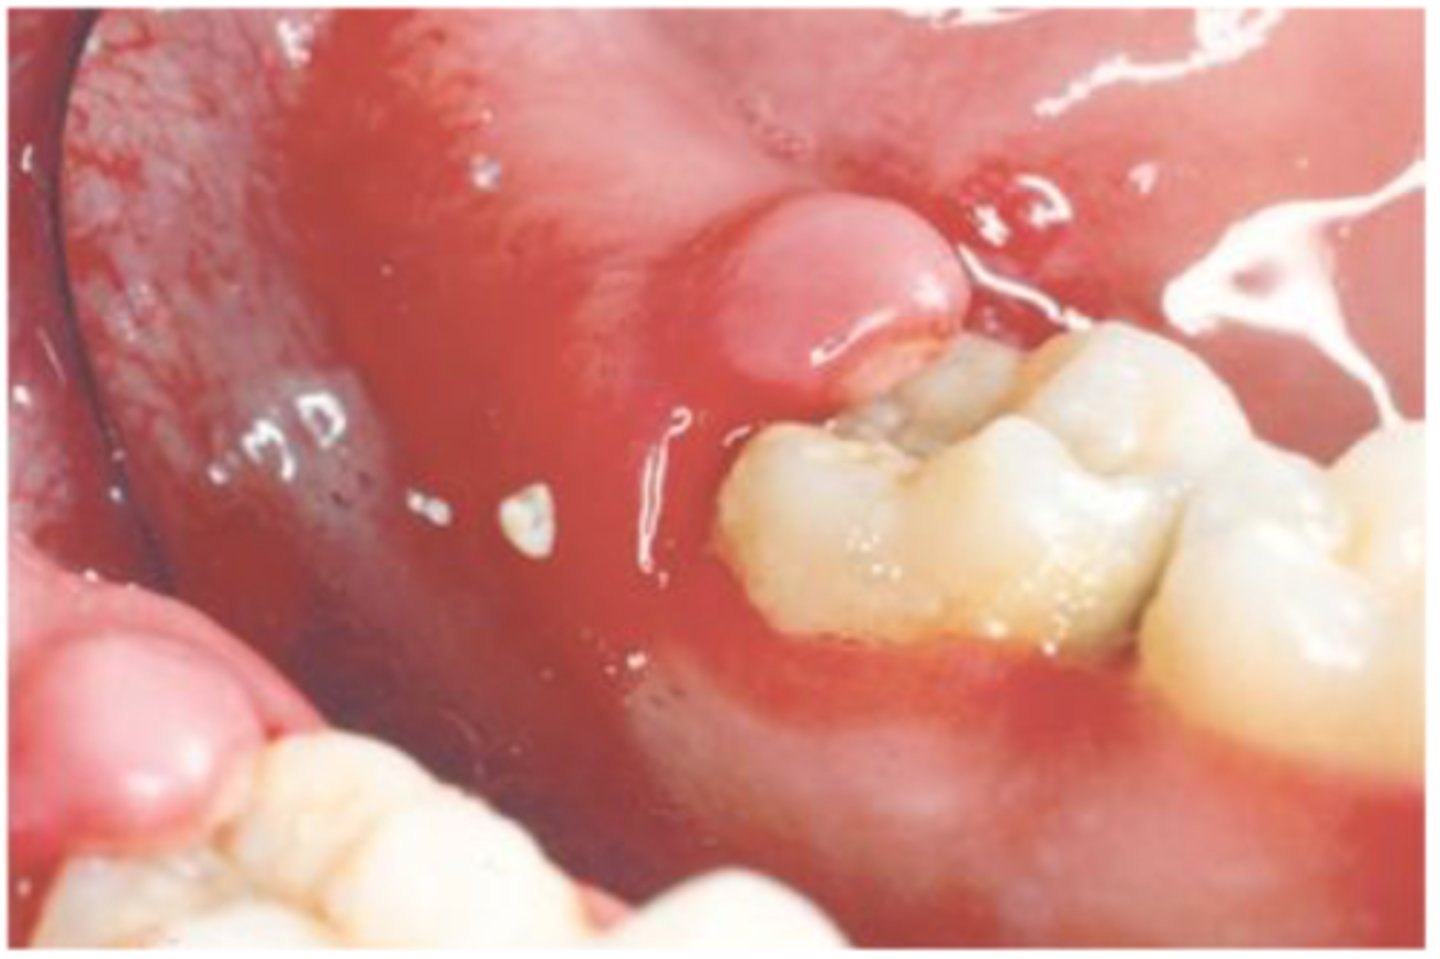

Pericoronitis

inflammation around the crown of a partially erupted tooth

Where is pericoronitis commonly found?

third molars

Radiographic features of pericoronitis

underlying osteitis

loss of cortical outline